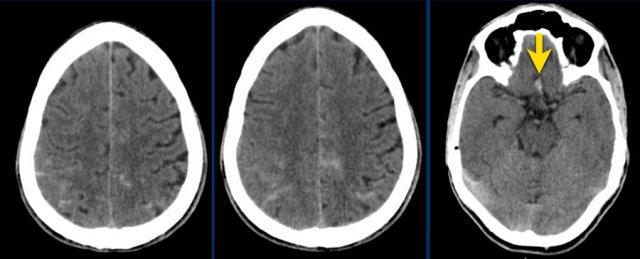

Đây là một ví dụ về xuất huyết dưới nhện trên NECT.

Lưu ý vị trí máu chủ yếu xung quanh thân não và trong não thất III và IV.

Thông thường, vị trí của máu dưới nhện giúp định hướng xác định vị trí của túi phình động mạch.

Bước tiếp theo là thực hiện chụp CT mạch máu (CTA) để tìm kiếm túi phình động mạch là nguyên nhân gây SAH.

Bệnh nhân này có túi phình tại nguyên ủy của động mạch tiểu não sau dưới trái (PICA).

Cũng cần lưu ý tình trạng não úng thủy.

Bệnh nhân này được thực hiện chụp mạch số hóa xóa nền (DSA) và sau đó được nút coil.

DSA cho thấy một túi phình hình túi của PICA trái, đường kính tối đa 6 mm với cổ ngắn và hẹp.